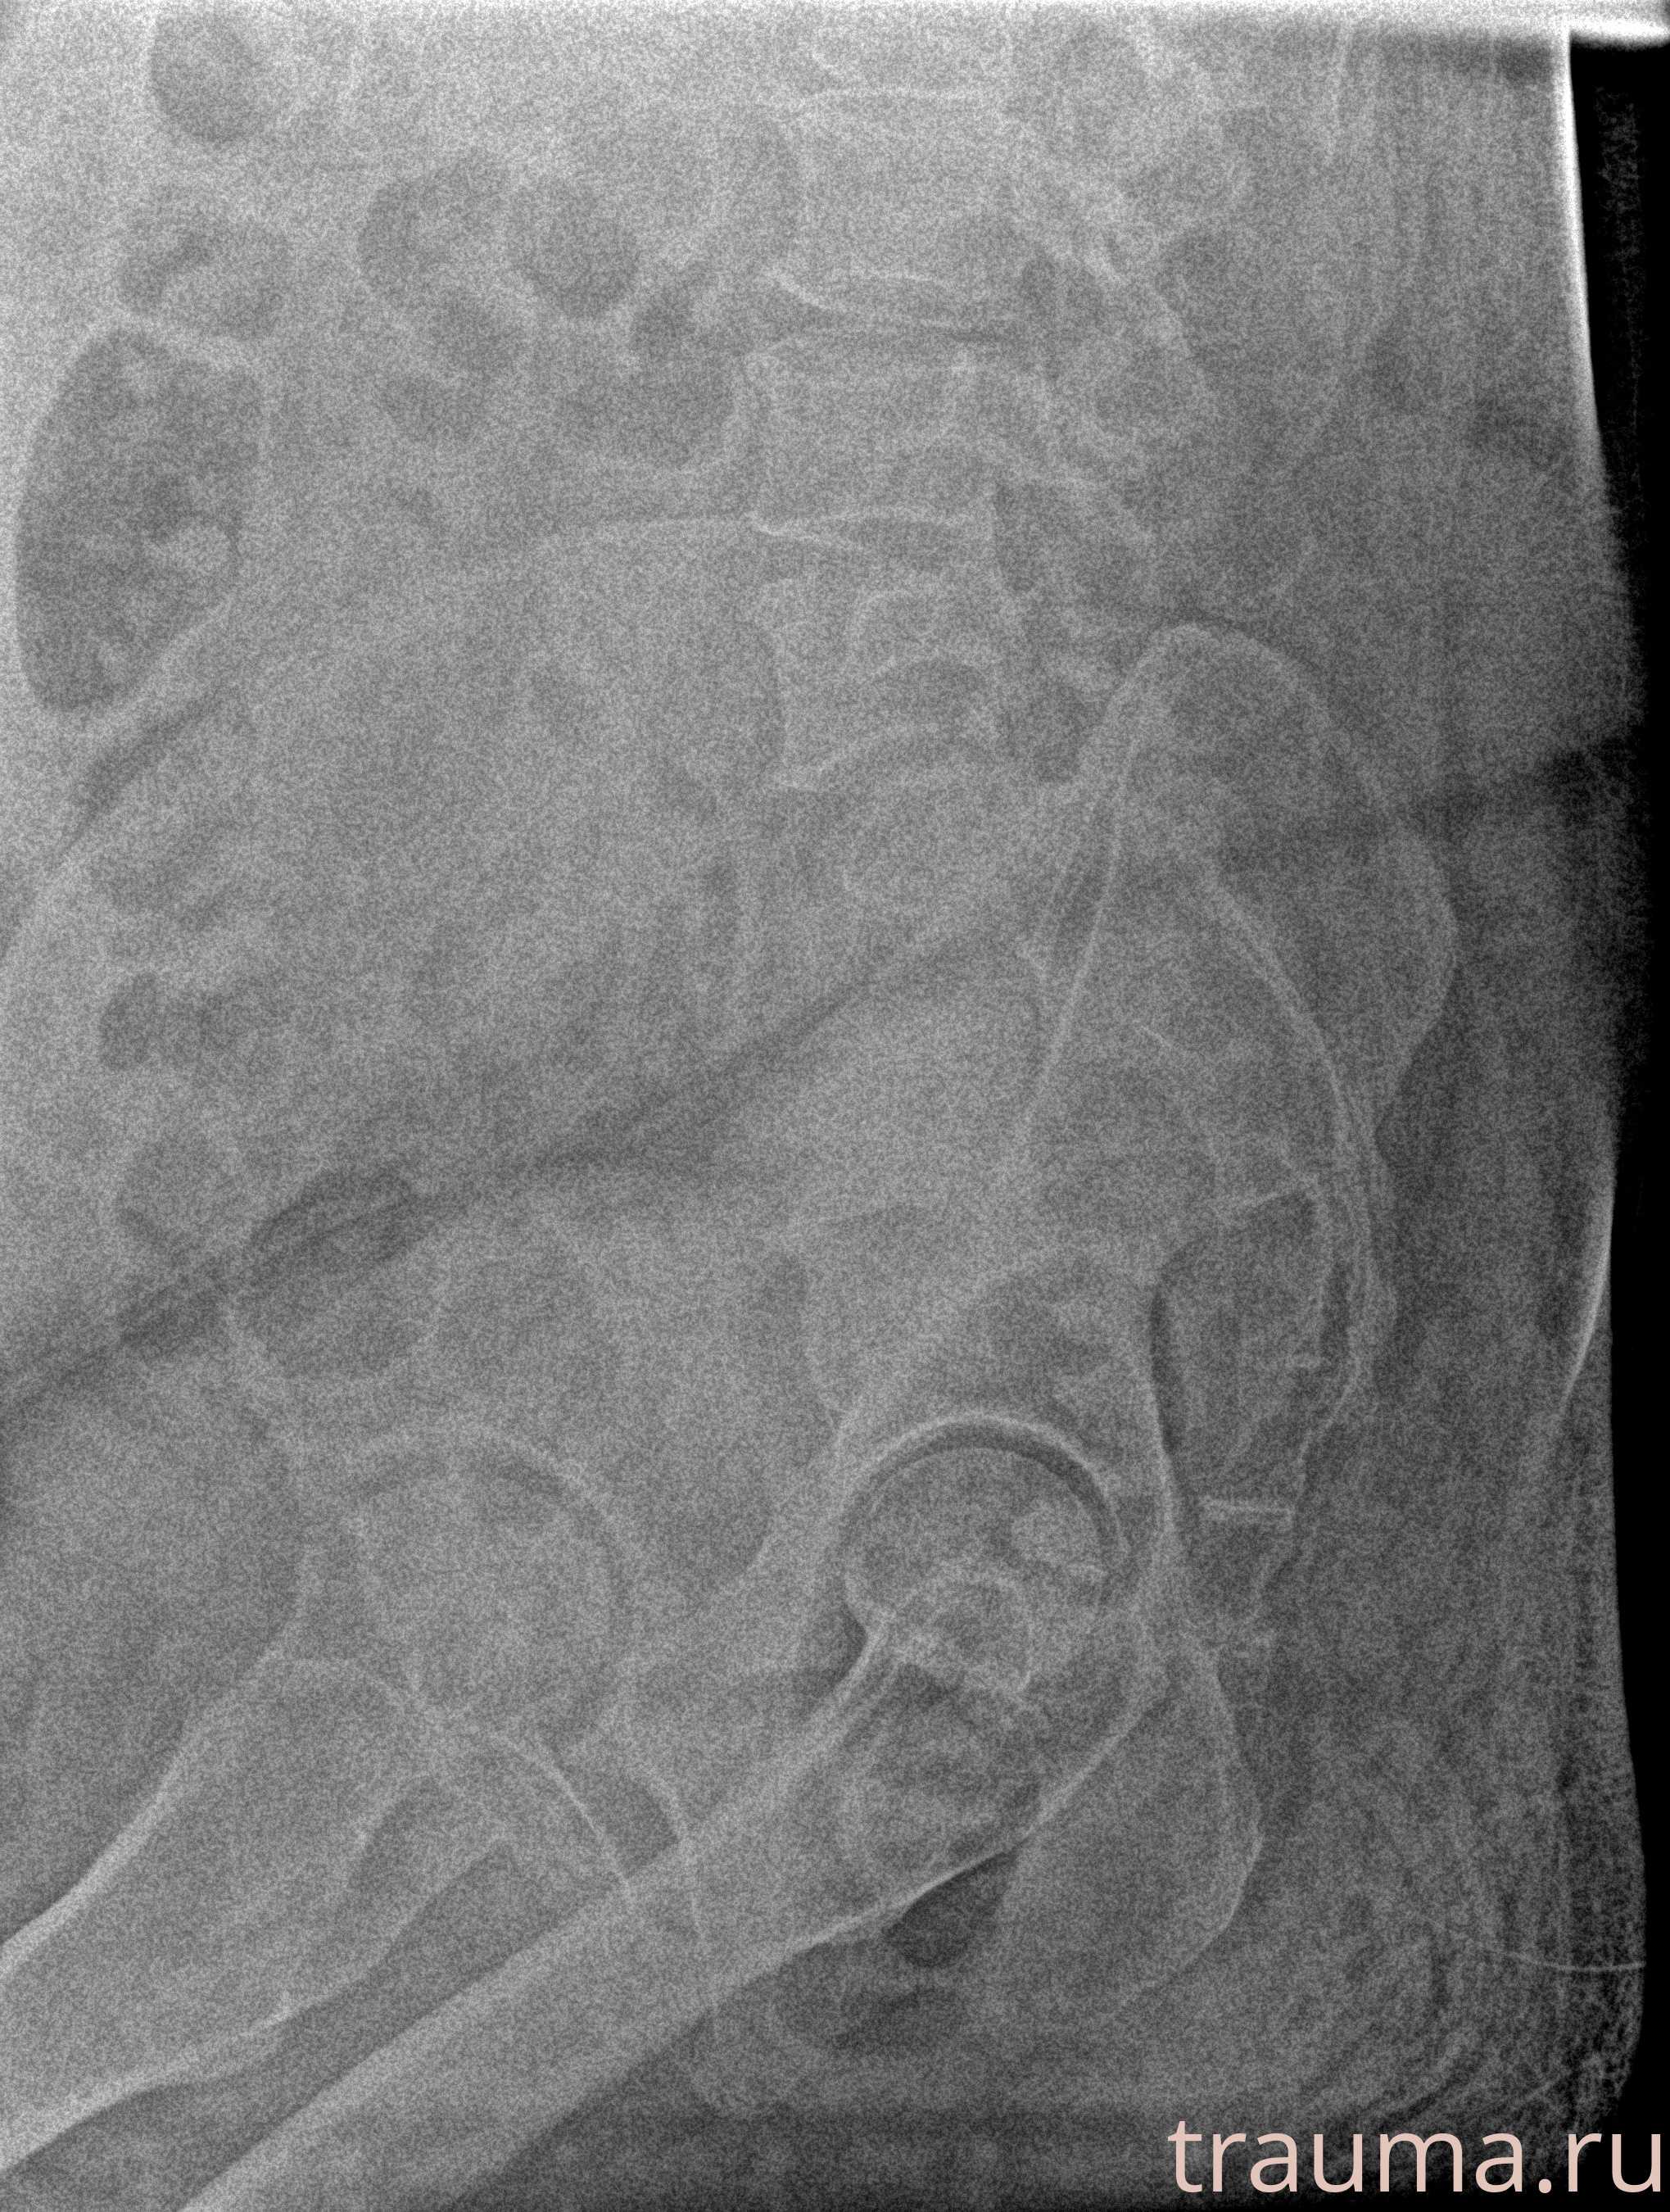

Рентген на дому: по вашему адресу приезжает врач-рентгенолог, травматолог-ортопед с мобильным рентгеновским аппаратом, проводит диагностику травмы или заболевания, делает необходимые рентгенограммы, дает рекомендации по дальнейшему лечению. Получить качественные снимки в домашних условиях возможно благодаря уникальной методике, разработанной МосРентген Центром для института  Склифосовского